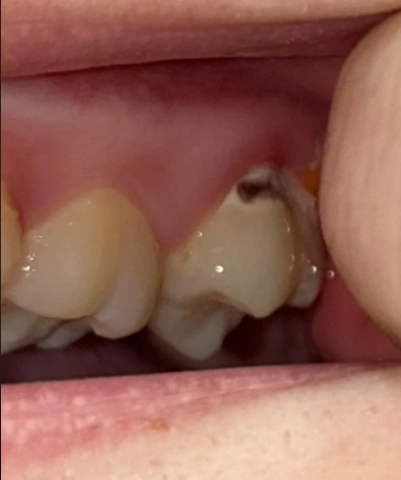

Severe Gumline Cavity and Tooth Discoloration Concern , Severe, Gumline, Cavity, Decay, Tooth, Discoloration, Yellowing, Exposed, Dentin, Treatment, Root, Canal, Crown, Dental, Emergency, Immediate, Appointment, Cebu, Philippines, General, Dentist

| Dark Spot | A significant, dark, black/brown area is visible on the upper/side of the tooth near the gum line. | Severe Dental Caries (Cavity): This indicates tooth decay, likely into the dentin, possibly approaching the pulp (nerve). |

| Yellowing | The surrounding tooth structure appears generally yellow/darker than the adjacent tooth. | Extrinsic Staining, Worn Enamel, or Exposed Dentin: While yellowing can be normal, if it is suddenly changing, it could mean the outer white enamel is thinning or has been removed by decay, exposing the naturally yellower dentin. |

| Gum Tissue | The gum tissue around the affected tooth appears slightly red/inflamed. | Gingivitis or Gum Irritation: Likely due to the proximity of the decay/plaque and/or poor brushing technique in the area. |

| Full Analysis & Diagnosis | Severe Dental Caries (Cavity), likely requiring immediate professional intervention. The decay appears deep and may extend to the pulp. The yellowing is likely secondary to this decay or exposed dentin. |

| Process to Execute | 1. Professional Examination: X-rays and visual inspection by a dentist. 2. Treatment: Likely a large filling, a dental crown, or if the nerve is affected, a root canal treatment followed by a crown. 3. Hygiene Review: The dentist will advise on proper brushing technique (non-abrasive, gentle strokes) and products. |

| Time Frame to "Heal" | 0 days for self-healing. This condition requires a professional procedure. The procedure itself might take 1-2 hours for a filling or root canal/prep, and then 1-2 weeks for a crown to be made and seated. |

| If it Takes 14 Days | What will be the issue that will scale up? Within 14 days, the decay will continue to advance, potentially reaching the tooth's pulp (nerve). This would lead to severe pain, infection (abscess), swelling, and could necessitate a more complex, painful, and costly root canal or even tooth extraction. |

Change in Color: The yellowing you are noticing is less concerning than the dark, black/brown spot near the gum line, which is a sign of serious decay.

Brushing: Ensure you are using a soft-bristled toothbrush and not scrubbing aggressively, as this can wear away the remaining enamel (abrasion), exposing more of the yellow dentin.